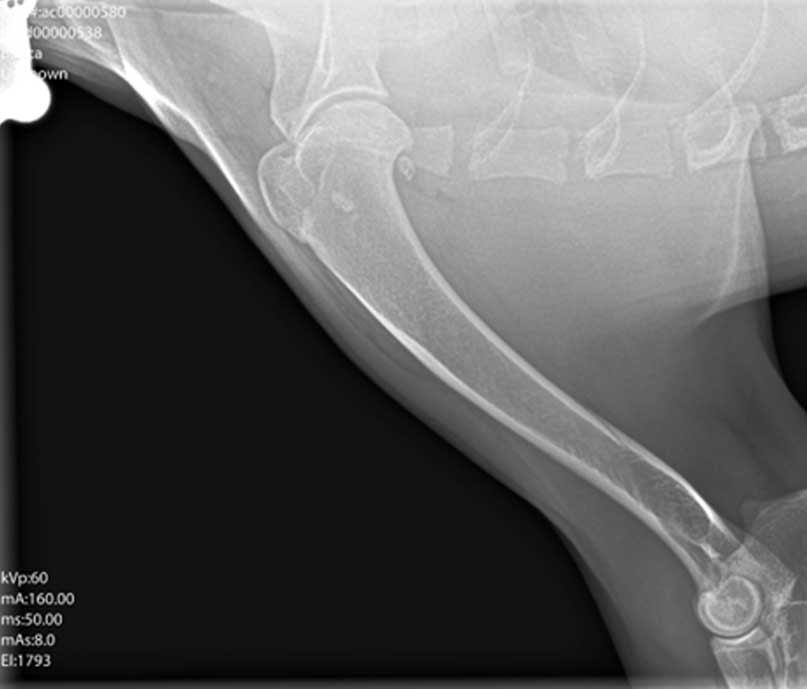

Dijagnoza se postavlja na temelju kliničkog pregleda i rendgenskih snimaka zahvaćenog zgloba. U određenim slučajevima koriste se i naprednije metode poput CT-a ili artroskopije radi preciznije procjene.